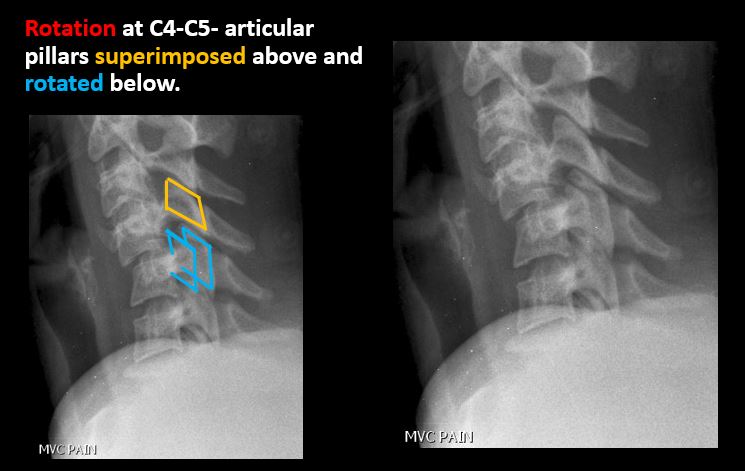

There is anterolisthesis, retrolisthesis, subluxation, or rotational abnormality of a disc space. |

Yes | NA |

There is widening, rotational abnormality, or displacement of facets at any motion segment (e.g. locked or jumped, perched facets, or fracture dislocation). |